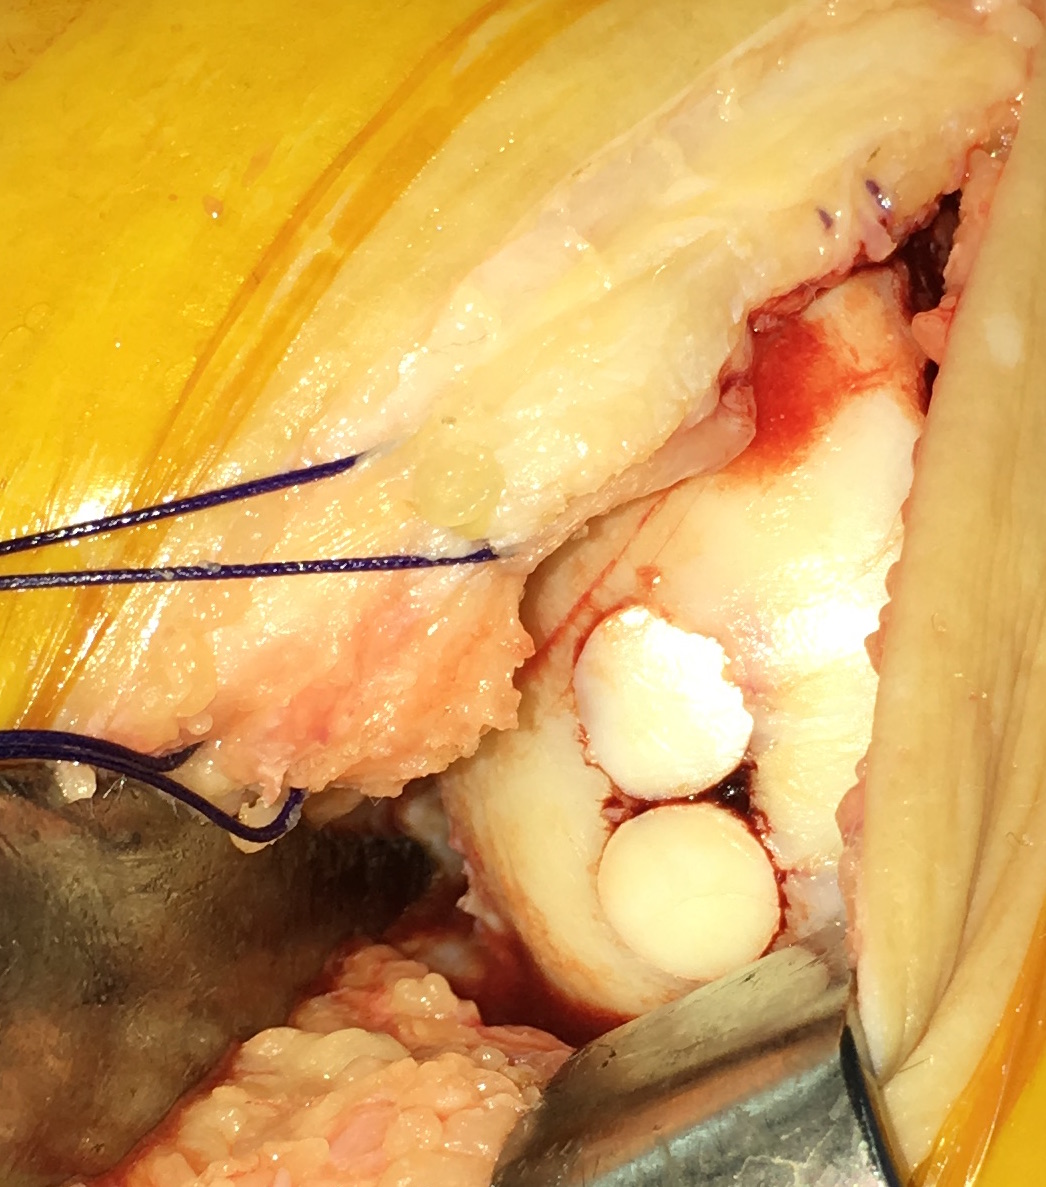

IntroducciónEl trasplante osteocondral autólogo es una alternativa quirúrgica en lesiones focales del cartílago articular. El objetivo de nuestro trabajo fue evaluar una serie de 62 pacientes tratados con mosaicoplastía de rodilla con 8 años promedio de seguimiento.Material y métodosEvaluamos retrospectivamente 62 pacientes operados con mosaicoplastía entre el año 2001 y 2014. Se incluyeron pacientes con lesión de cartílago focal de la rodilla a los que se les realizó mosaicoplastía aislada o asociada a otros procedimientos quirúrgicos (reconstrucción de LCA, osteotomía). Con un seguimiento mínimo de 2 años. Se evaluaron con las escalas de Lysholm e IKDC y el grado de artrosis con la escala radiográfica de Kellgren-Lawrence.ResultadosCuarenta y cinco fueron hombres y 17 mujeres. La edad promedio fue de 36 años. Treinta y cinco en cóndilo interno, 12 cóndilo externo, 12 tróclea y 3 combinadas. Cuarenta y dos fueron mosaicoplastías aisladas y 20 asociados a otro procedimiento. El resultado promedio de la escala de Lysholm al momento de la evaluación fue 80.1 y el IKDC fue 66.7. No encontramos diferencias significativas en la escala de Lysholm e IKDC entre los grupos de mosaicoplastía aislada y asociada a otro procedimiento. En 30 pacientes evaluados con radiografía se observó una inclusión satisfactoria del taco óseo.ConclusionesDentro de las opciones quirúrgicas se encuentran las microfracturas, el auto/alo injerto osteocondral y el implante de condrocitos autólogos. Todas estas técnicas han demostrado mejorar el estado clínico en comparación con el estado preoperatorio independientemente de cuál se utilice. En nuestra serie de pacientes operados con mosaicoplastía encontramos resultados satisfactorios en las evaluaciones clínicas.Consideramos que la mosaicoplastía es un procedimiento con alto grado de satisfacción y buenos resultados funcionales en pacientes con lesiones focales del cartílago articular. AbstractIntroduction: Osteochondral autograft transplantation is a surgical alternative for osteochondral defects of the knee. The aim of this study was to analyze a series of 62 patients treated with osteochondral autograft transplantation of the knee and an average follow-up of 8 years.Methods: A total of 62 patients treated with osteochondral autograft transplantation between 2001 and 2014 were evaluated. Patients with focal osteochondral lesions who underwent osteochondral autograft transplantation alone or associated with another procedure and a minimum follow-up of 2 years were included. Lysholm score, IKDC, and Kellgren- Lawrence radiographic scale were used. Forty-five men and 17 women (average age 36 years) were evaluated. Lesions were localized in medial condyle (35), lateral condyle (12), patella (12), and three were combined. Forty-two patients underwent isolated osteochondral autograft transplantation while 20 patients underwent associated surgical procedures.Results: Mean Lysholm score was 80.1 and IKDC score was 66.7. There were no significant differences in the Lysholm and IKDC scores between groups. Radiographic results demonstrated complete graft incorporation in 30 patients. Clinical evaluation revealed satisfactory results.Conclusion: Osteochondral autograft transplantation to treat osteochondral lesions is a procedure with a high clinical satisfaction and good functional results in patients with focal osteochondral lesions.Descargas